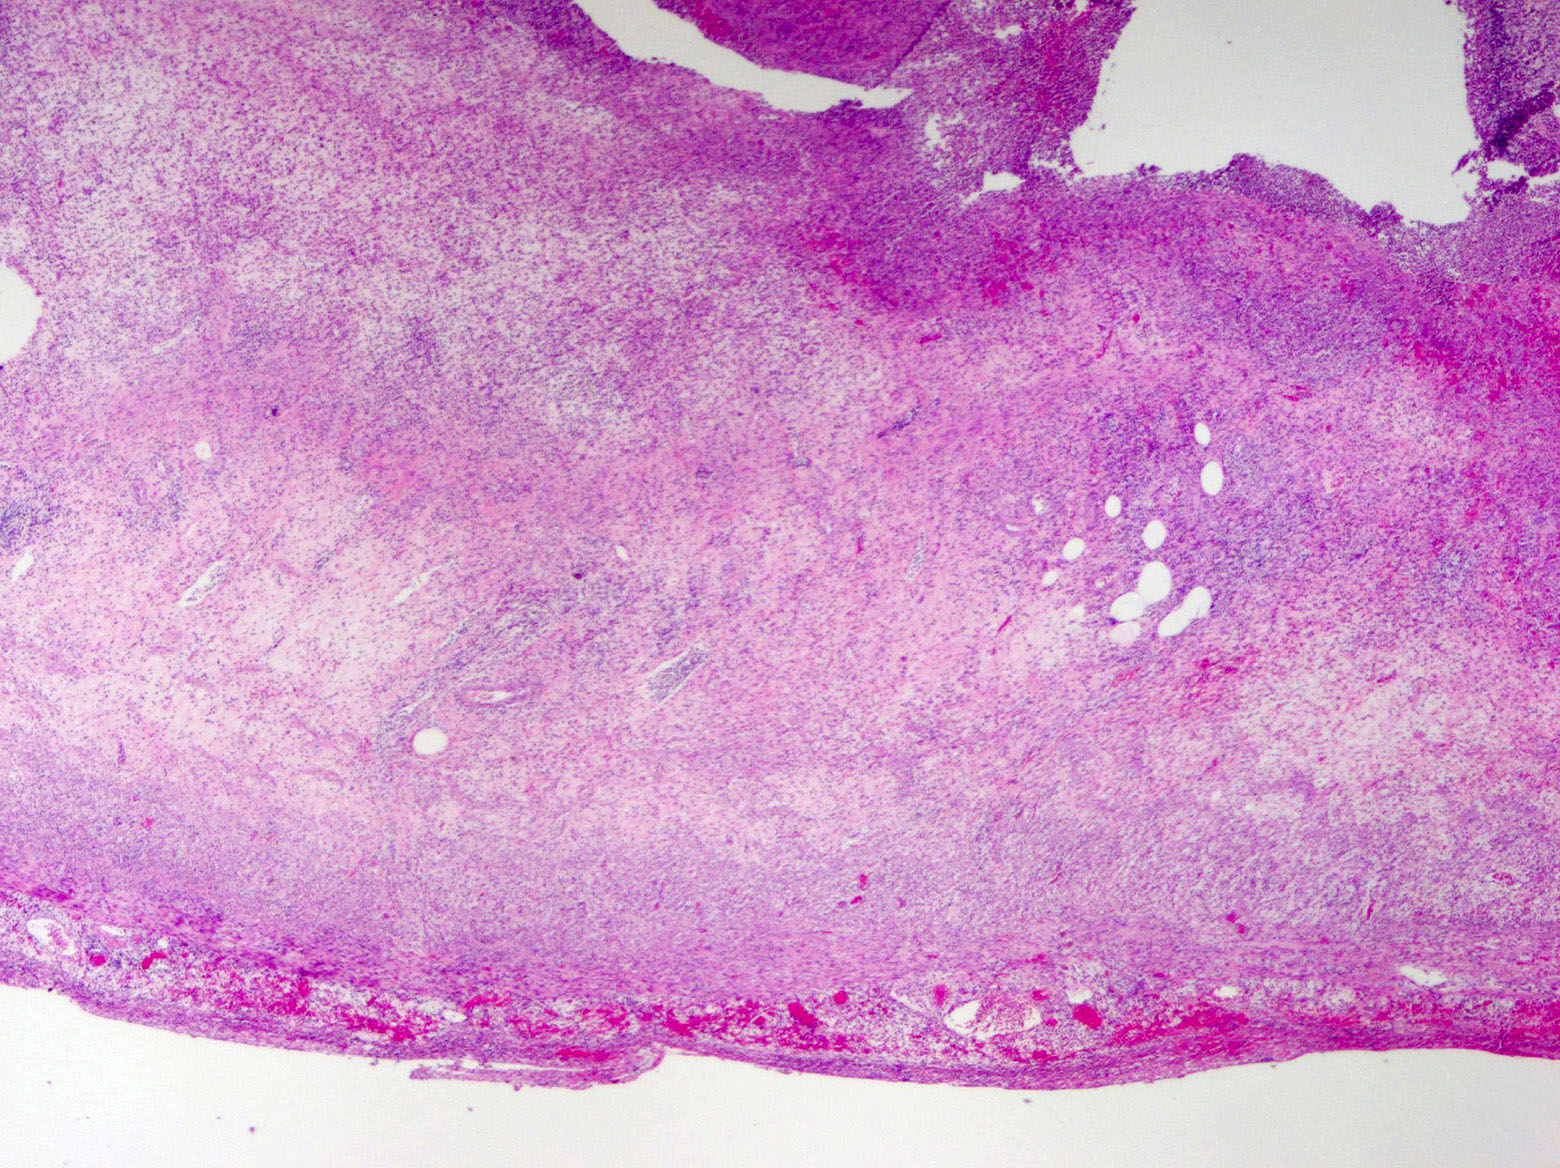

Gross description

- Gross and microscopic extent of inflammation may not correlate

- Inflammation may involve entire appendix or only a segment

- Appendix may appear grossly normal when inflammation is limited to the mucosa and submucosa

- Appendix appears swollen and erythematous when inflammation extends into the muscularis propria

- When the serosa is affected, a purulent exudate appears

- Cut surface may show hyperemia or intraluminal or intramural abscess

- Appendiceal wall may be completely necrotic in gangrenous appendicitis (J Pediatr Surg 2019;54:718)

- Perforation in severe cases

Microscopic (histologic) description

- Variable acute inflammation with predominance of neutrophils; involves some or all layers of the appendiceal wall

- Process may be divided into acute focal, acute suppurative, gangrenous and perforative

Microscopic (histologic) images

A 40 year old caucasian man presented into the emergency room with right lower quadrant pain associated with vomiting, abdominal tenderness, fever and moderate leukocytosis. Acute appendicitis was suspected and he underwent an appendectomy. His appendix was sent to pathology for histological evaluation. The H&E images are shown above. Which of the following is the most likely diagnosis?